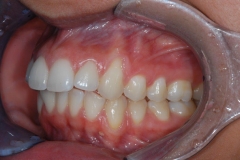

This mouth had recession on just one tooth with very little bone to support the tooth. The area needed support and thickness. The tissue was placed and the area now has thicker tissue to withstand the forces that the patient needs to place on it.

Click on a thumbnail to view the before and after photos.